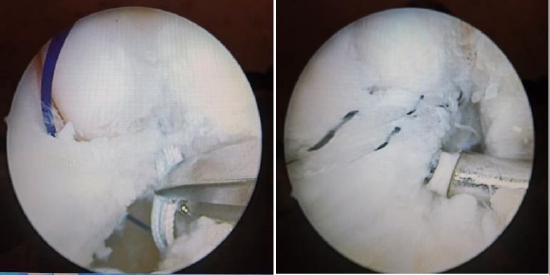

以肩袖损伤的病人为例,很多患者可以进行肩关节镜微创手术来进行治疗,效果非常好。关节镜手术是将具有照明装置的透镜金属管通过很小的切口由自然腔隙进入关节腔内,可以在高清显示器监视下非常直观的观察关节腔内的病变情况和严重程度,全面检查和清理修复病损,是一种兼具诊断和治疗两种功能的微创技术。

肩关节镜手术

1、外伤和退变性疾患:最常见的是肩袖损伤、还有冻结肩(以往俗称“肩周炎”)、肩峰下撞击综合症、钙化性肌腱炎、肩锁关节炎、肩关节游离体、滑膜软骨瘤病以及各种原因引起的滑膜炎,等等。

2、肩关节不稳定:肩关节习惯性脱位、急性肩关节脱位相关的盂唇损伤、关节盂骨性损伤以及肩锁关节脱位的微创治疗等。